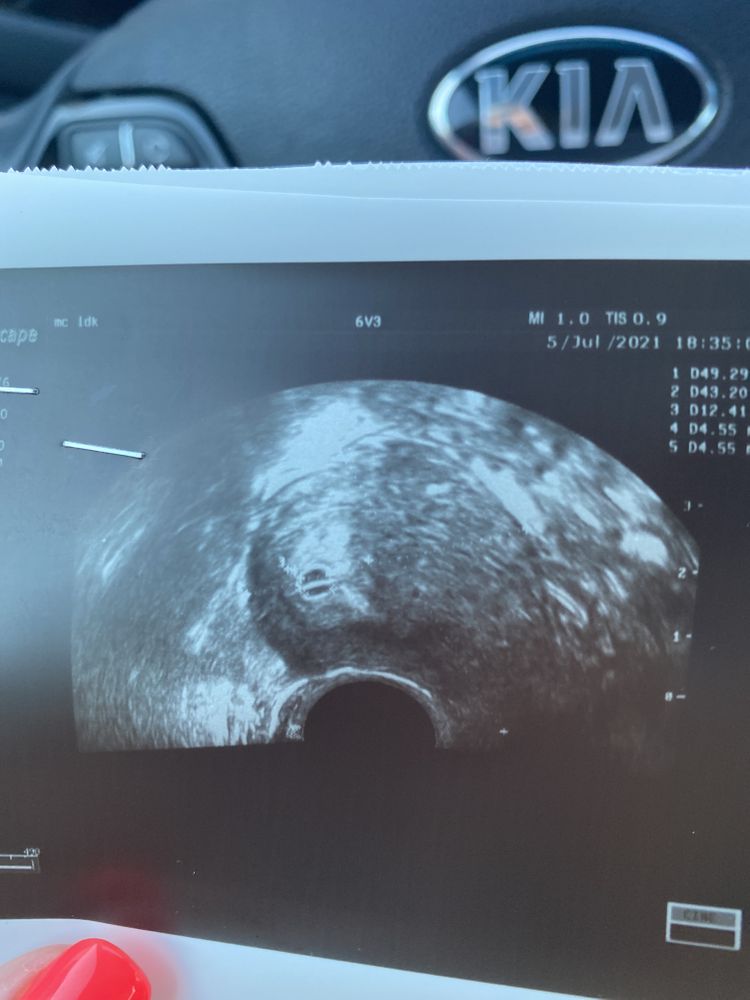

Аня, да посмотрим. Там плодное яйцо такое интересное, либо перегородка прям, либо сердечко сбоку. Она крутила, крутила. С ракурса как на фото прям перегородку видно.

Аня, два, сразу на узи было